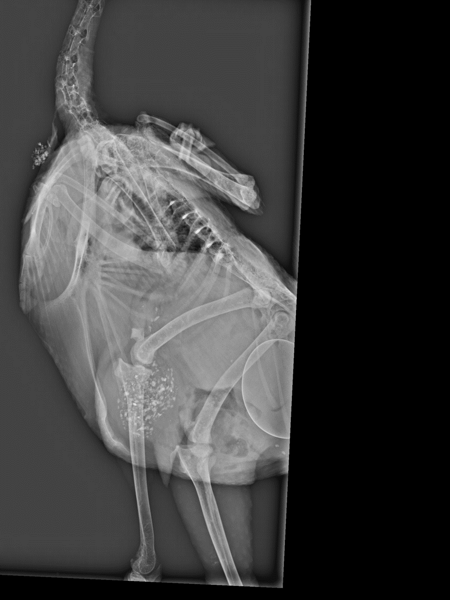

Skador på bröstbenet, såsom frakturer och böjningar, är vanliga hos både vita och bruna värphöns, oavsett hur de hålls. Forskare vid SLU har undersökt hur effektiv röntgenundersökning är för att upptäcka bröstbensskador, och om storleken hos hönans bäckenben har samband med skadorna.

Resultaten visar att röntgenundersökning av bröstbenets form och tjocklek är en bra metod för att upptäcka bröstbensskador, särskilt när det gällde deformationer. Det fanns ett samband mellan bentäthet och bröstbensskador, men kopplingen var inte så stark. Hönor med större bäckenhålor drabbades oftare av bröstbensskador. Ett ökat inre tryck från bäckenhålan på bröstbenets insida kan ge frakturer och deformationer i bröstbenet.

Genom röntgenundersökning i produktionsbesättningar kan hönornas benhälsa mätas på ett tillförlitligt sätt. Det skulle också kunna användas som avelsmetod, vilket kan leda till friskare och mer motståndskraftiga värphöns och förbättrad djurvälfärd i framtiden.